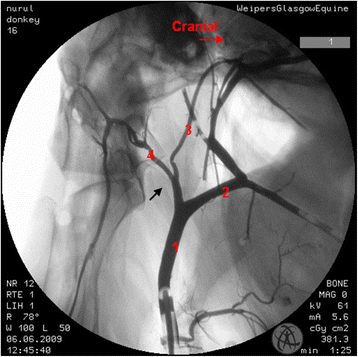

Where there were differences in the angiographic appearance in comparison to horses, these variations affected the termination of the common carotid artery. Sharing of a common trunk with the occipital and the internal carotid arteries was observed unilaterally in one donkey (Fig. 2). Five angiograms demonstrated the linguofacial trunk originating from the common carotid artery (Fig. 3). In another five angiograms, it appeared that the linguofacial trunk shared a common origin with the external carotid artery (Fig. 4).

Lateral angiogram of the left carotid arterial tree of a donkey shows variation from the common pattern of this structure where the occipital and the internal carotid arteries share a common trunk (black arrow). 1 common carotid artery; 2 external carotid artery; 3 internal carotid artery; 4 occipital artery